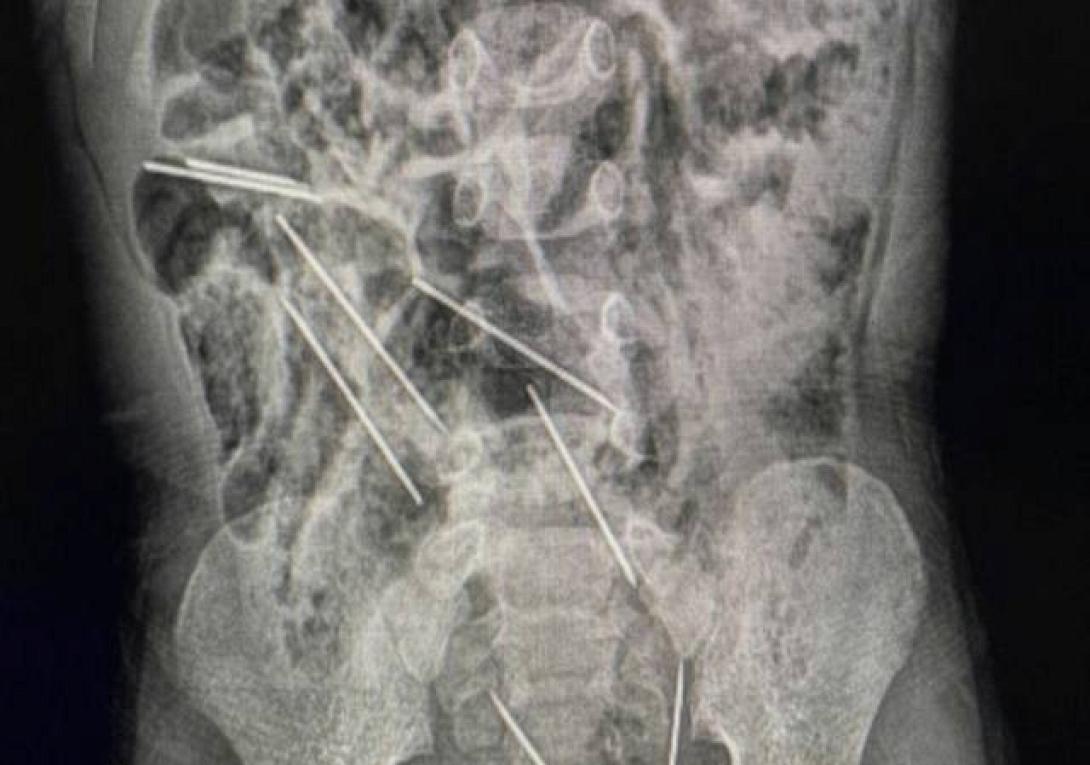

Αγόρι κατάπιε οκτώ μεγάλες βελόνες από ενέσεις για ζώα

ακτινογραφία

Οι γιατροί στο βορειοανατολικό Περού έσωσαν τη ζωή ενός αγοριού 2 ετών που κατάπιε οκτώ βελόνες ενέσεων ενώ έπαιζε.

«Μόλις βρεθήκαμε στο χειρουργείο και ανοίξαμε την κοιλιά του, βρήκαμε μεταλλικά κομμάτια και συνειδητοποιήσαμε ότι ήταν όντως βελόνες δήλωσε ο Δρ. Εφρέν Σάλαζαρ από νοσοκομείο του Περού.